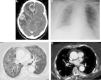

We report the case of a 69-year-old woman with a diagnosis of multifocal GM (Fig. 1A), who presented with a clinical picture of fever and rapidly progressing respiratory failure, 4 weeks after starting temozolomide and high-dose corticosteroids. Chest radiograph (Fig. 1B) showed increased ground glass density in both lungs, which was confirmed on chest computed tomography (CT) (Fig. 1C). An incidental finding was bilateral pulmonary thromboembolism (Fig. 1D). PJP was suspected, so fiberoptic bronchoscopy was performed which confirmed PJP in bronchoalveolar lavage. The patient responded favorably, both clinically and radiologically, to anticoagulants and antibiotic treatment with trimethoprim–sulfamethoxazole.

(A) Axial CT image of the head, after administration of intravenous contrast medium, showing 2 intra-axial ring enhancing lesions (arrows) in the left cerebral hemisphere, with a significant mass effect and associated perilesional edema. (B) Anteroposterior chest radiograph showing ground glass opacities in both lungs. (C) Axial image of chest CT (lung window), showing a noteworthy mosaic pattern in the pulmonary parenchyma, with areas of ground glass attenuation alternating with others of less density, typical of Pneumocystis jirovecii infection. (D) Axial image of chest CT (mediastinum window) with intravenous contrast (obtained at the same level as image C), showing central filling defect in the right lower lobe artery (arrow), associated with pulmonary thromboembolism.